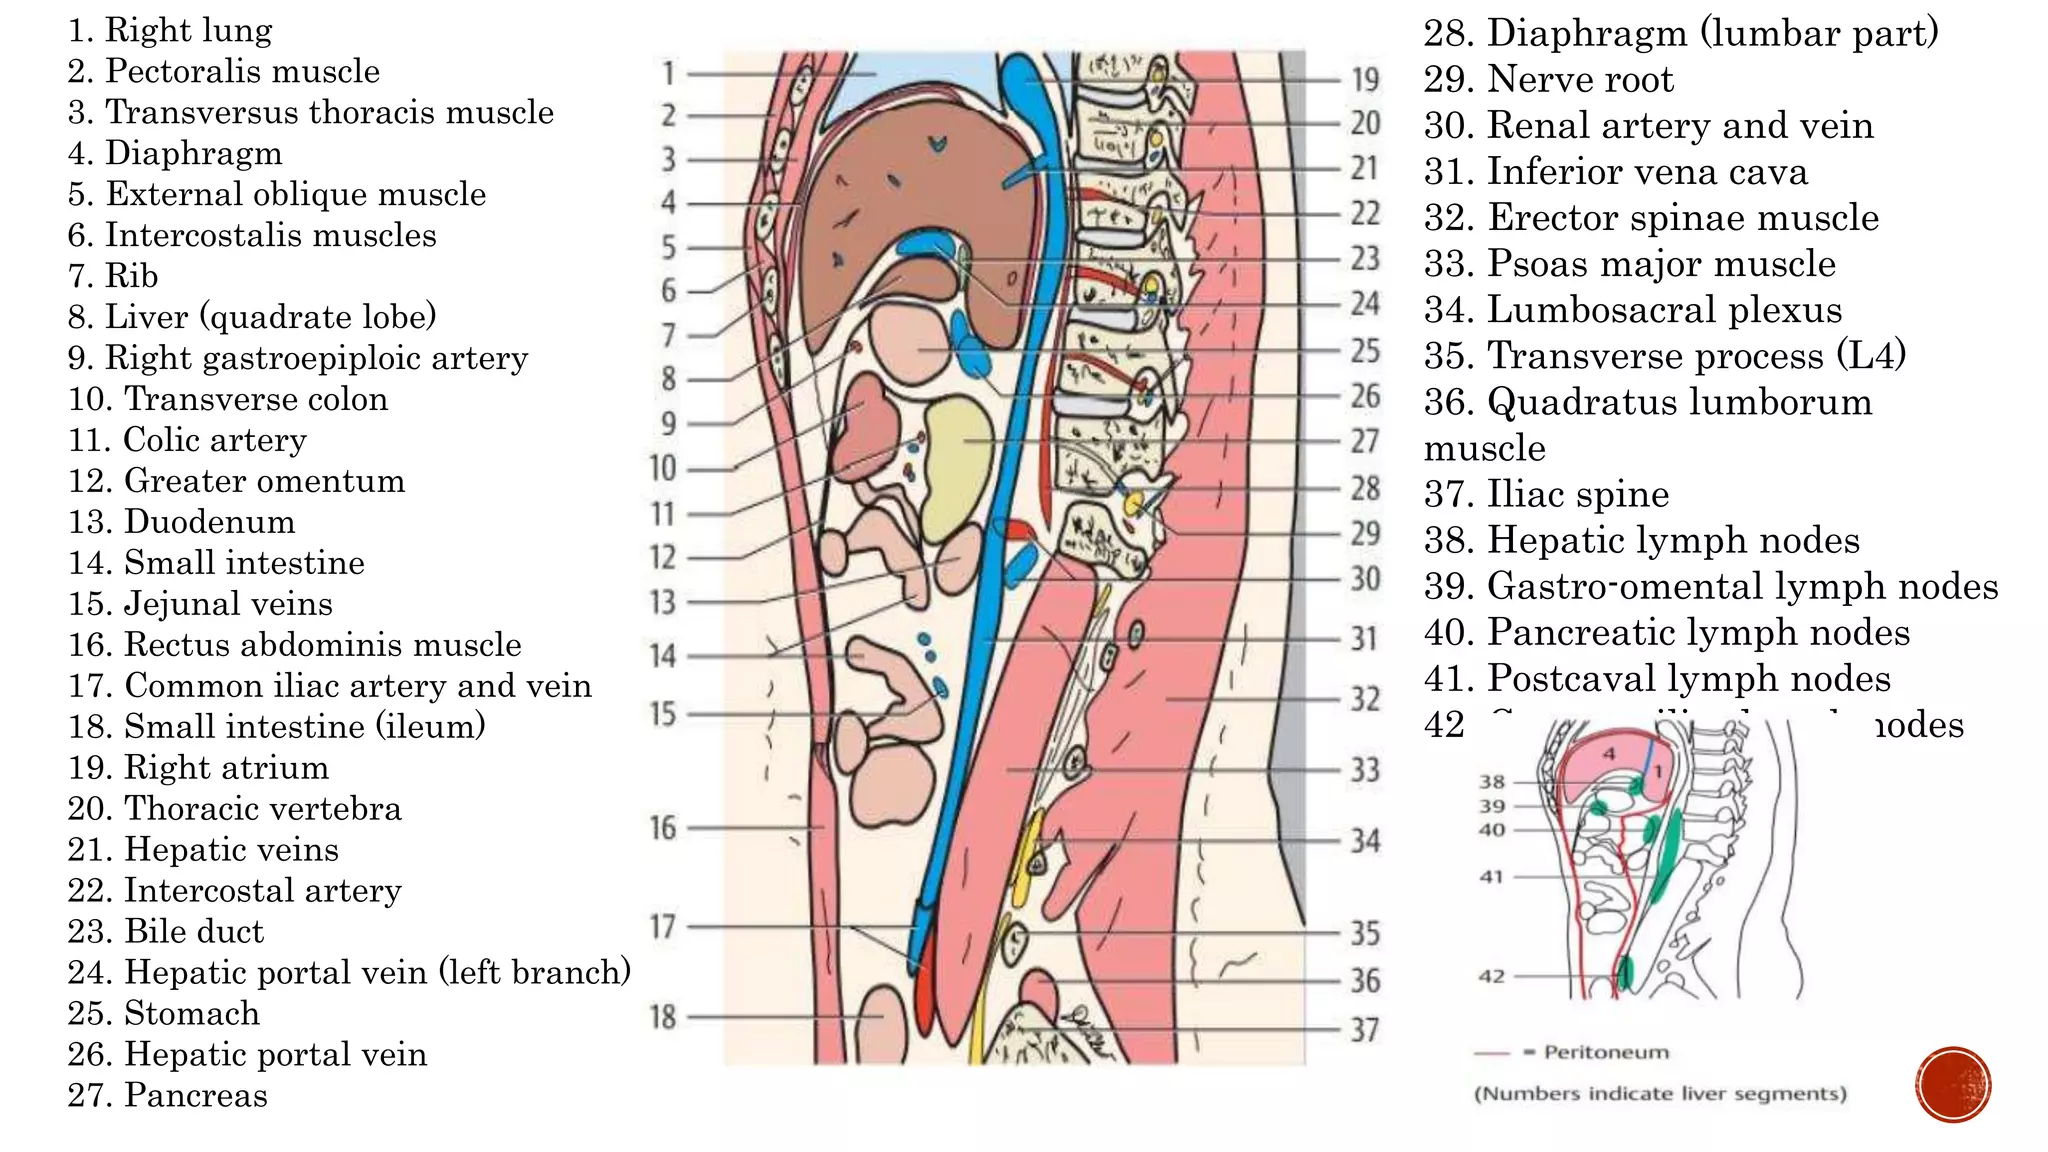

The document describes the anatomy of the abdomen and pelvis region of the human body. It lists over 40 structures and their locations, including major organs like the liver, kidneys, intestines, blood vessels and muscles of the abdominal wall and pelvis. The structures are grouped into sections focusing on different anatomical areas like the abdomen, retroperitoneum, pelvis and gluteal region.